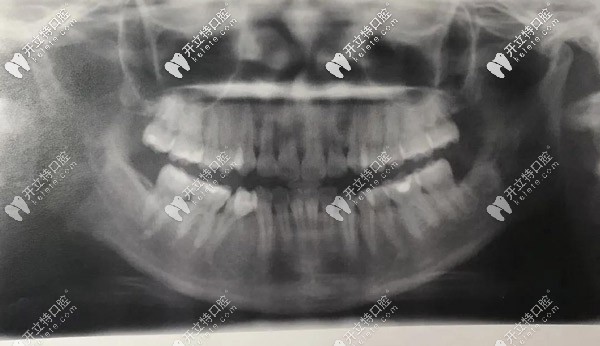

全口X光,牙齒很不齊

▲全口X光,牙齒很不齊